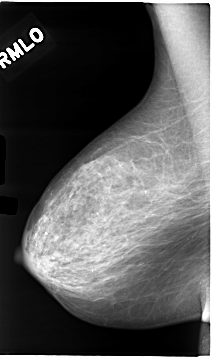

C_0049_1.RIGHT_MLO

RIGHT_CC LINES 4728 PIXELS_PER_LINE 2680 BITS_PER_PIXEL 12 RESOLUTION 50 NON_OVERLAY

RIGHT_MLO LINES 4664 PIXELS_PER_LINE 2744 BITS_PER_PIXEL 12 RESOLUTION 50 NON_OVERLAY